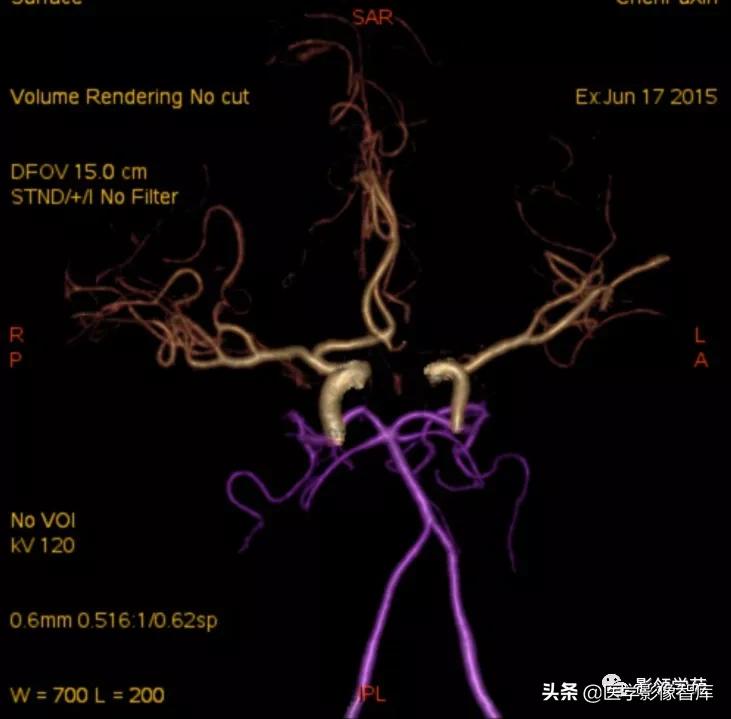

女 58岁,头晕、呕吐,桥脑右前方见一类圆形

高低混合(有血栓)T1及T2信号影,边界清楚、锐利。

明显不均匀强化(瘤内有血栓)。与基底动脉分界不清

头颅CTA:基底动脉起始部血管局部瘤样突起(宽基底),无占位效应。